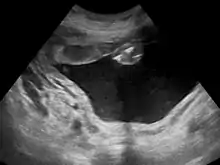

اگر پزشک به پلی هیدرآمنیوس مشکوک باشد ابتدا یک سونوگرافی از جنین انجام میدهد. او با اندازهگیری بزرگترین و عمیقترین پاکه اطراف جنین، حجم مایع آمنیوتیک (AFV) را تخمین میزند. اگر مقدار AFV از ۸۰۰ میلیمتر بیشتر بود به معنی ایجاد پلی هیدرآمنیوس میباشد.

گاهی وقتها نیز برای اندازهگیری میزان مایع آمنیوتیک مقدار آن را در چهار قسمت از رحم شما که بیشترین عمق مایع را دارد اندازه میگیرند. به مجموع این اندازهگیریها شاخص مایع آمنیوتیک (AFI) گفته میشود که اگر بیشتر از ۲۵ سانتیمتر شود به معنی وجود پلی هیدرآمنیوس است.[4]